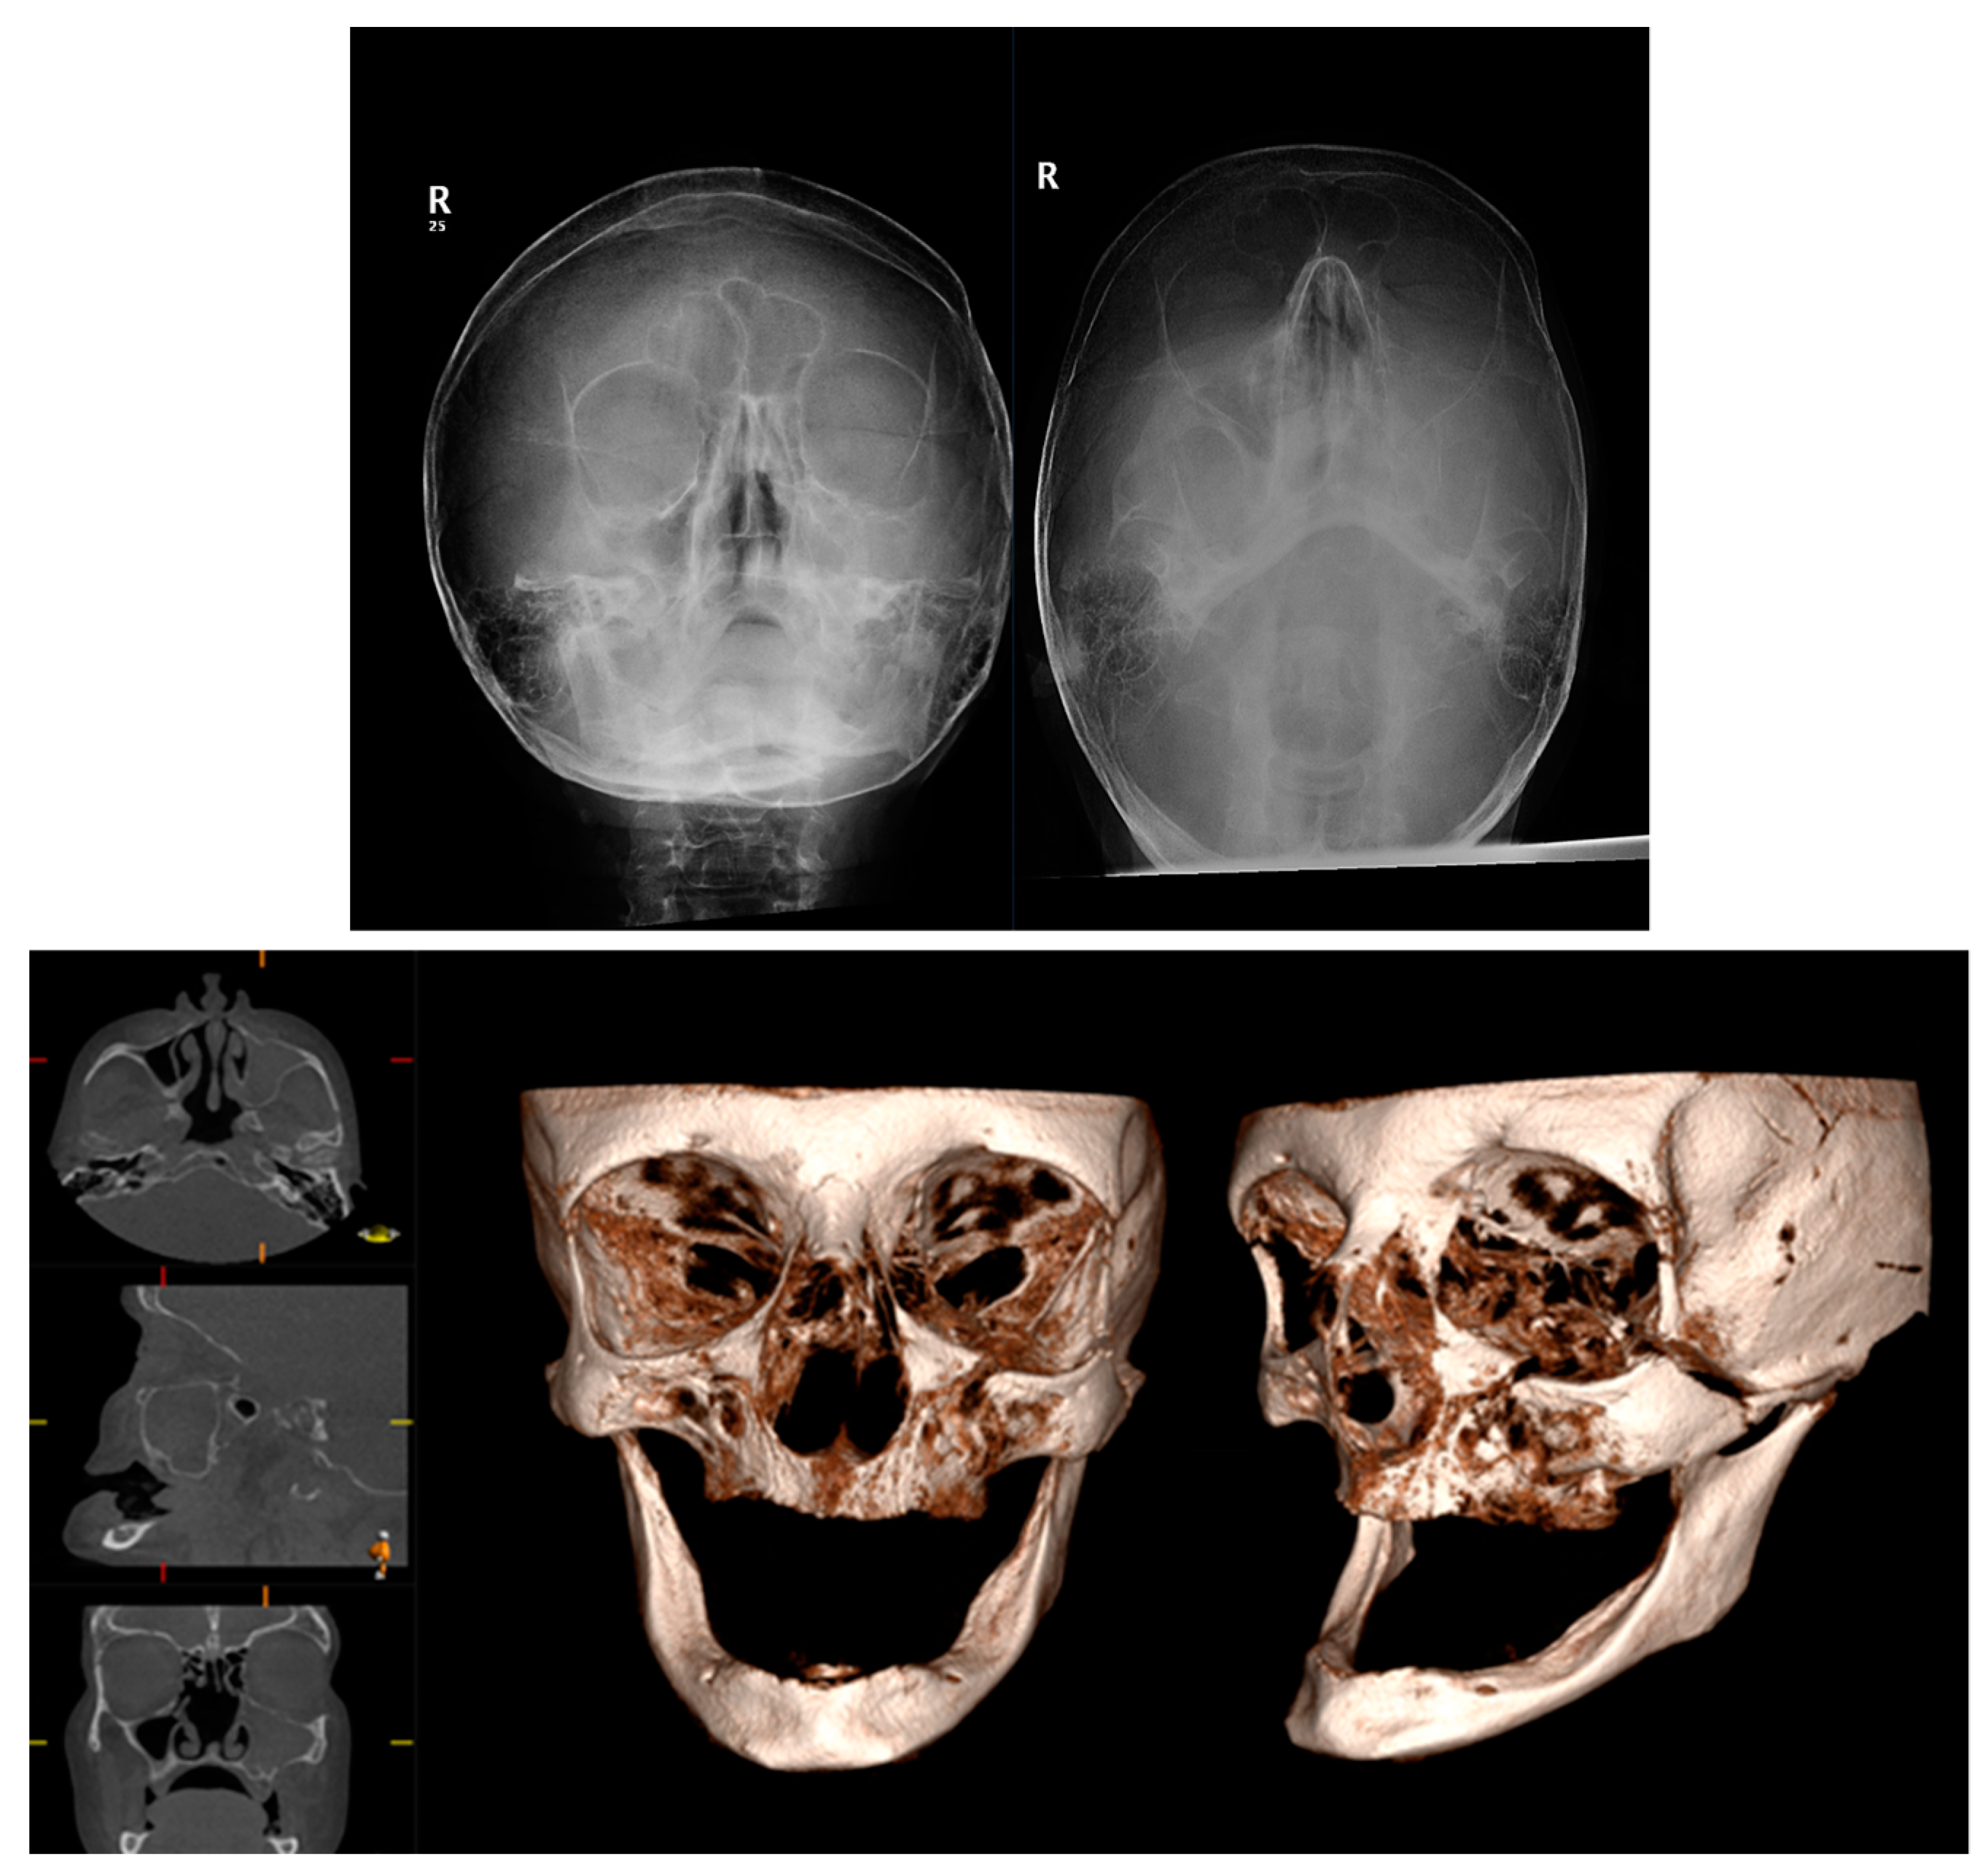

3.6. Cone Beam CT for Assessment Fractures of the Zygomatic Maxillary Complex and Midface

The zygoma is the second-most commonly fractured facial fracture after nasal bone fractures. It contributes to the structure of the midface, articulating with several bones of the craniofacial skeleton, and thus fractures can be associated with significant functional and aesthetic morbidity. In the last decade, conventional CT has replaced occiptomental plain radiographs as the gold standard for imaging assessment. The ability to review imaging in multiple planes can aid the surgeon in understanding the direction of displacement to plan the reduction and fixation required for stability. Figure 6 demonstrates the difficulties with interpreting OM views owing to the superimposition of anatomical structures. The left zygomatic complex fracture is much better visualised on CBCT-reconstructed images.

Figure 6.

Occipitomental views and CBCT axial, sagittal, coronal, and 3D reformatted images demonstrating a fracture to the left zygomatic complex. Conventional occipitomental views are difficult to interpret owing to superimposition. CBCT-reformatted images show the comminuted nature of the fracture and also allow for visualization of the orbital floor.

Similarly, midface fractures comprising a Le Fort Pattern are best appreciated with cross-sectional imaging. These fractures often accompany a multi-injured patient, and thus conventional CT is more readily utilised in non-ambulatory and comorbid patients. Otherwise, CBCT can show a larger number of fracture lines and fragments [40], and 3D printing can facilitate surgical planning, the alignment of teeth, and the construction of custom arch bars without the need for impressions. In our unit, CBCT is often utilised to assess fracture reduction post fixation (Figure 7). This serves as a baseline post-operative image and a more reliable assessment of bone reduction than a plain X-ray.

Figure 7.

Pre-operative CT 3D volume renders and post-operative CBCT axial, sagittal, coronal slices, and 3D volume render showing reduction and fixation of fractures through the symphysis mandible, Le Fort 1 level, and maxillary alveolar bone.